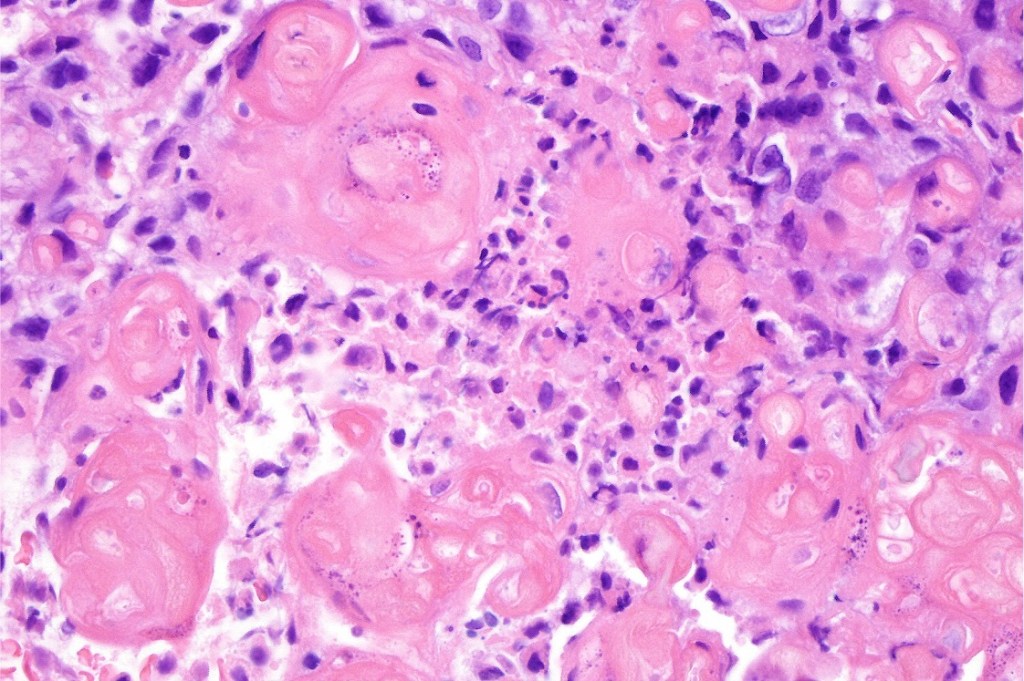

•Basaloid population with prominent nucleoli accompanied by supramatricial and ghost cells

Melanocytic matricoma should be differentiated from pigmented pilomtricoma. This is much nore common and is characterized by pigmented dendritic cells and pigmented matrical cells in the abscence of any mitotic activity or pleomorphism in the melanocytic population. However, there can be considerable overlap.